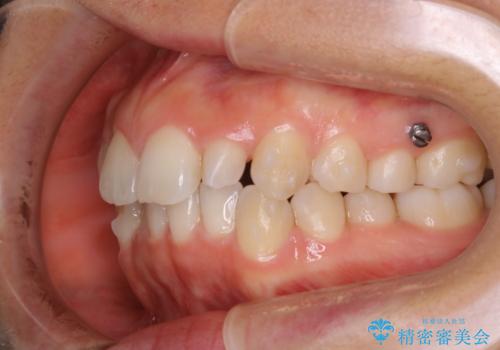

- 上の前歯が大きい事と下の前歯のがたつきを気にされてご相談にいらした方です。上の2番目の歯が矮小歯であったため、矯正治療にて歯のスペースを作った後、矮小歯には被せ物をして前歯のバランスを整えました。

歯科技工士さんとの打ち合わせを重ね、周囲の歯としっかりなじむ天然歯のような被せ物をお作りすることが出来ました。

矯正治療と補綴治療をうまく組み合わせることで、美しい口元に仕上げることが出来ました。矯正治療、補綴治療をまとめて行える総合歯科治療を体現した治療といえます。